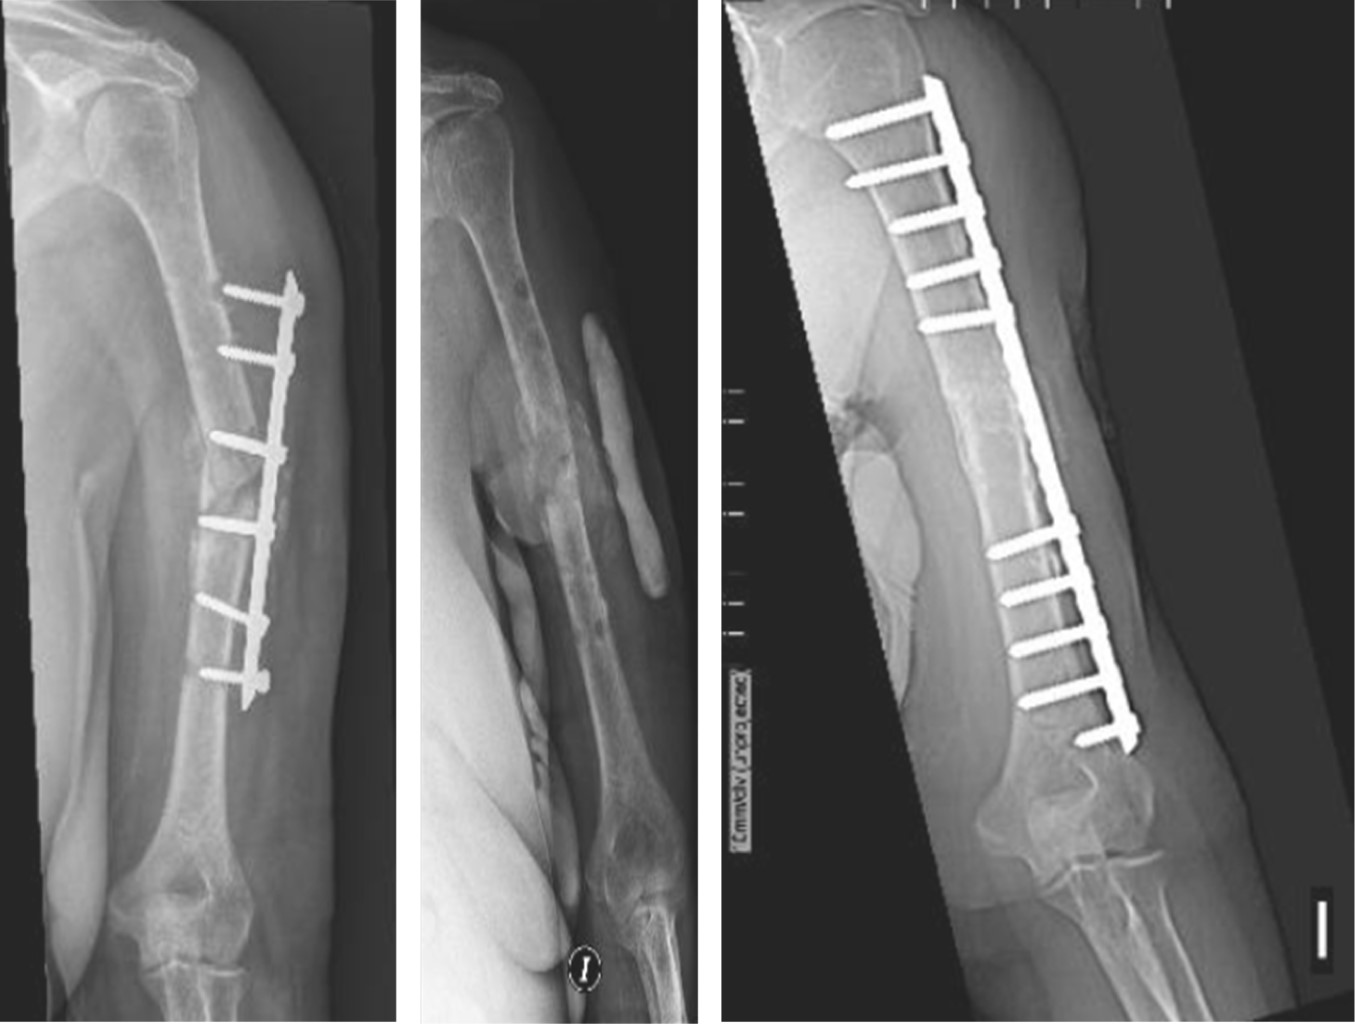

El miembro superior derecho estaba comprometido en nueve pacientes y el izquierdo en 13; el miembro dominante fue el afectado en 10 casos. El tercio proximal de la diáfisis humeral estaba involucrado en ocho pacientes, el tercio medio en otros ocho, el tercio distal en cuatro y dos pacientes presentaban no-consolidaciones segmentarias de la diáfisis humeral (Figura 1). El tiempo desde el trauma inicial hasta el tratamiento definitivo de la no-consolidación promedió 18 meses (rango: 6 a 51). El tratamiento inicial había sido conservador con yeso o brace termoplástico en cuatro pacientes y en 18 el tratamiento inicial fue quirúrgico; 12 pacientes habían tenido una cirugía previa, tres habían tenido dos cirugías previas, dos habían tenido tres cirugías con anterioridad y un paciente había tenido cuatro cirugías previas (Tabla 1). Al momento de realizar la última cirugía, ocho pacientes presentaban un dispositivo endomedular (seis clavos rígidos y dos clavos elásticos), nueve tenían una placa y en un paciente el implante había sido removido. En 16 de estos 17 casos los implantes fueron removidos en la cirugía definitiva; en un caso, que había sido tratado con clavo endomedular, en el cual la fractura evolucionó hacia la no-consolidación, la estabilización definitiva se realizó con una placa puente LCP larga de 3.5 mm, sin remover el clavo endomedular. Al momento de la cirugía definitiva, tres pacientes presentaban infección activa y tres presentaban antecedente de infección previa. Las reconstrucciones en los tres casos con infección activa fueron realizadas en dos etapas, siguiendo la técnica de la membrana inducida por cemento, descrita por Pelissier y colaboradores para reconstrucción de defectos óseos infectados (Figura 2).13

Se asoció injerto óseo en todos los casos; en 17 no-consolidaciones solo injerto óseo esponjoso autólogo de cresta ilíaca (16 de cresta ilíaca anterior y uno de cresta ilíaca posterior), en tres casos se utilizó aloinjerto (estructural en uno y triturado en dos) y en dos fueron combinados aloinjerto estructural e injerto óseo esponjoso autólogo de cresta ilíaca anterior (Figura 1). Las tablas de aloinjerto fueron colocadas endomedulares en dos casos (Figura 1); y en uno se colocaron tablas de aloinjerto tanto endomedular como extramedular (Figura 3). En todos los casos se asoció al injerto óseo dos gramos de vancomicina en polvo colocada localmente a nivel de la no-consolidación.

Las no-consolidaciones atróficas no son avasculares24 y parte de la estrategia de tratamiento en estas no-consolidaciones debe enfocarse en crear un lecho adecuado y estimular la osteogénesis a nivel del foco de no-consolidación.25 En nuestra serie, en todos los casos se realizó decorticación osteoperióstica con escoplos a nivel de la no-consolidación para reactivar la osteogénesis y osteoinducción. El uso de injerto óseo es recomendado en no-consolidaciones atróficas o en presencia de defectos óseos;26 y cuando el aumento biológico es considerado necesario, el injerto óseo autólogo sigue siendo el estándar de oro en no-consolidaciones de húmero.6,17,27,28,29,30 En nuestra serie utilizamos injerto óseo en los 22 casos, autoinjerto esponjosos de cresta ilíaca en 17 casos, aloinjerto en tres y una combinación de autoinjerto y aloinjerto en dos; obteniendo buena osteointegración en todos los casos. Las dos críticas comúnmente realizadas al uso de aloinjertos estructurales en no-consolidaciones son el riesgo incrementado de infección y una mayor agresividad con los tejidos blandos; sin embargo, diferentes autores han reportado altos porcentajes de consolidación sin riesgo elevado de infección utilizando aloinjertos estructurales asociados a osteosíntesis.17,18,31,32,33,34 Las tablas de aloinjerto actúan como férulas internas, cubren defectos óseos intramedulares o extramedulares, proveen soporte estructural, ayudan a la estabilidad de la osteosíntesis e incrementan la fuerza de agarre de los tornillos, lo que incrementa la fuerza y resistencia de la construcción.26,35 Los aloinjertos tienen la ventaja de reducir la morbilidad del sitio dador y el tiempo quirúrgico, siendo particularmente beneficiosos en defectos óseos significativos;6,30 pero el uso rutinario de aloinjertos óseos está limitado, por su baja disponibilidad y por la escasa experiencia de los cirujanos en su uso; y estudios prospectivos de mayor calidad son necesarios para poder determinar qué tipo de injerto óseo o sustituto óseo es ideal para cada no-consolidación. En nuestra serie utilizamos aloinjerto molido en dos casos y aloinjerto estructural en tres no-consolidaciones; las cinco no-consolidaciones eran asépticas. El aloinjerto esponjoso molido de cabeza femoral fue indicado en dos pacientes de sexo femenino, con cirugías previas, en las que autoinjerto de cresta ilíaca ya había sido utilizado; y siendo informadas de las ventajas y desventajas del uso de aloinjerto, ambas decidieron por el uso del mismo; en estos dos casos se prefirió aloinjerto molido porque el contacto óseo obtenido intraoperatoriamente entre los cabos a nivel de la no-consolidación fue bueno, pero el defecto parcial resultante de los implantes flojos de las cirugías previas era significativo e irregular. En los tres casos que se utilizó aloinjerto estructural utilizamos tablas de peroné divididas longitudinalmente y colocadas intramedulares (en uno de estos casos una segunda tabla de aloinjerto fue colocada por debajo de una placa moldeada en onda) (Figura 3). Los pacientes en que se utilizaron tablas de aloinjerto tenían marcada osteoporosis, con una cortical humeral muy fina en toda su extensión; uno de estos casos presentaba no-consolidación segmentaria. El uso de injertos óseos vascularizados, ya sea de peroné o injertos óseos pediculados como el recientemente descrito por Zaidenberg y colaboradores, tienen mejor indicación en no-consolidaciones recalcitrantes, con defectos óseos segmentarios mayores;29 su utilización en pacientes mayores puede generar controversias por las comorbilidades de los enfermos, el tiempo quirúrgico y la morbilidad del sitio dador. En nuestra serie asociamos dos gramos de vancomicina en polvo de manera local a nivel del foco de no-consolidación en todos los casos, una vez terminada la reconstrucción y antes de cerrar los tejidos blandos; su utilización la basamos en el hecho de que ha demostrado ser efectivo en fracturas expuestas;30 en nuestros pacientes no hubo ninguna complicación relacionada con su empleo, todas las no-consolidaciones evidenciaron unión ósea y ninguna no-consolidación se infectó.